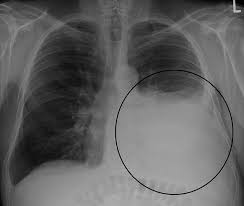

Рентгенологическое исследование

поджатое легкое на рентгенеДовольно часто закрытый пневмоторакс затруднительно достоверно определить, исходя из одних лишь симптомов и физикального обследования. В таких случаях точный диагноз ставится после изучения рентгеновских снимков пораженной области.

Сделанная в стационаре рентгенограмма легких и плевральной полости позволяет с высокой степенью точности выявить спонтанный пневмоторакс по областям воздушных скоплений на снимке.

Рентгенологические признаки, которыми проявляется пневмоторакс на рентгенограмме в прямых и боковых проекциях, представлены:

• просветленными областями из-за спадения легочной ткани;

• легочной рисунок плохо виден или не просматривается совсем;

• снимок, сделанный на вдохе, отличен от снимка на выдохе (заметно небольшое распрямление легкого).

Часто на рентгене запечатлено разной степени спадения поджатое легкое, смещенное в сторону средостения.